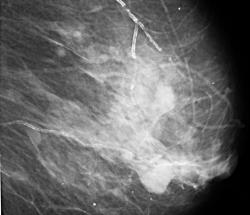

Бабуля 1926 г.р. сделала ММГ 1-й раз, жалобы на боли.

Похоже на локальную фиброзно-кистозную мастопатию, желательно бы еще выяснить нет ли у нее выделений из сосков и не было ли травмы мол. железы.

По всем канонам, и с учетом действующего приказа МЗиСР, пациентке обязаны делать биопсию, возможно под контролем УЗИ.